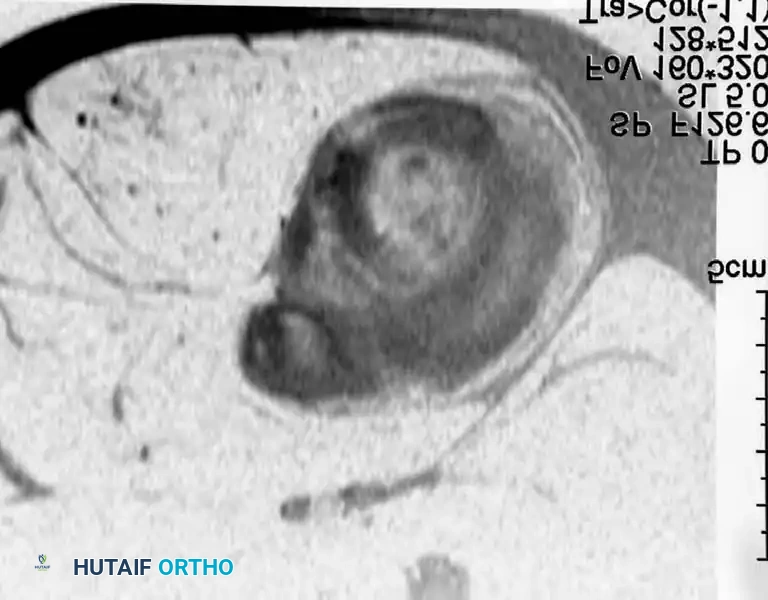

BENIGN TUMORS AND TUMOR-LIKE LESIONS Surgical Diagram

MRI of diffuse PVNS showing characteristic low-signal intensity on T2-weighted images due to profound hemosiderin deposition. Intraoperative view demonstrates the hypertrophic, villous, rust-colored synovium.